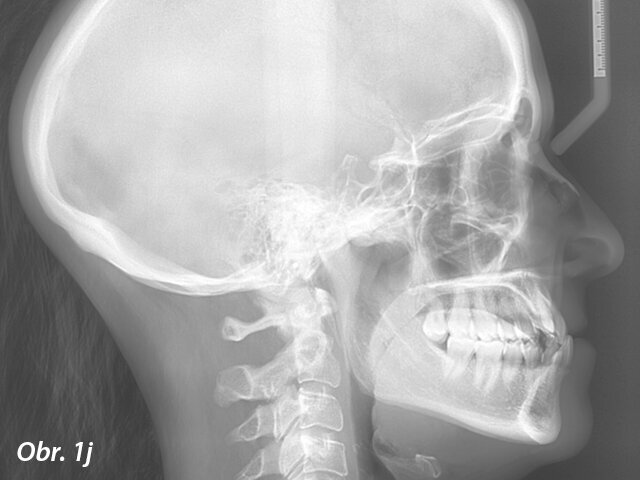

Diagnóza a léčebný plán

Pacientkou byla 30letá žena s konkávním profilem daným hypoplazií horní čelisti s krátkým horním rtem, prominencí dolního rtu, tupým nasolabiá­lním úhlem a skeletální III. třídou s maxilární retrognacií a mandibulární progenií. Co se týče dentálního nálezu, byla u pacientky diagnostikována III. třída s výrazným stěsnáním, obrácený skus, posun střední čáry o 1 mm, nevýrazná Speeova křivka a ageneze horních laterálních řezáků potvrzená na panoramatickém rentgenovém snímku (obr. 1a–j; tab. 1).